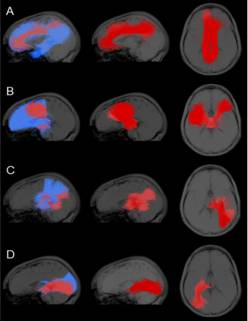

图1 帕金森氏病患者、无多巴胺能缺陷患者与正常人部分纤维簇的扩散指标对比

图2 部分纤维簇的可视化显示图